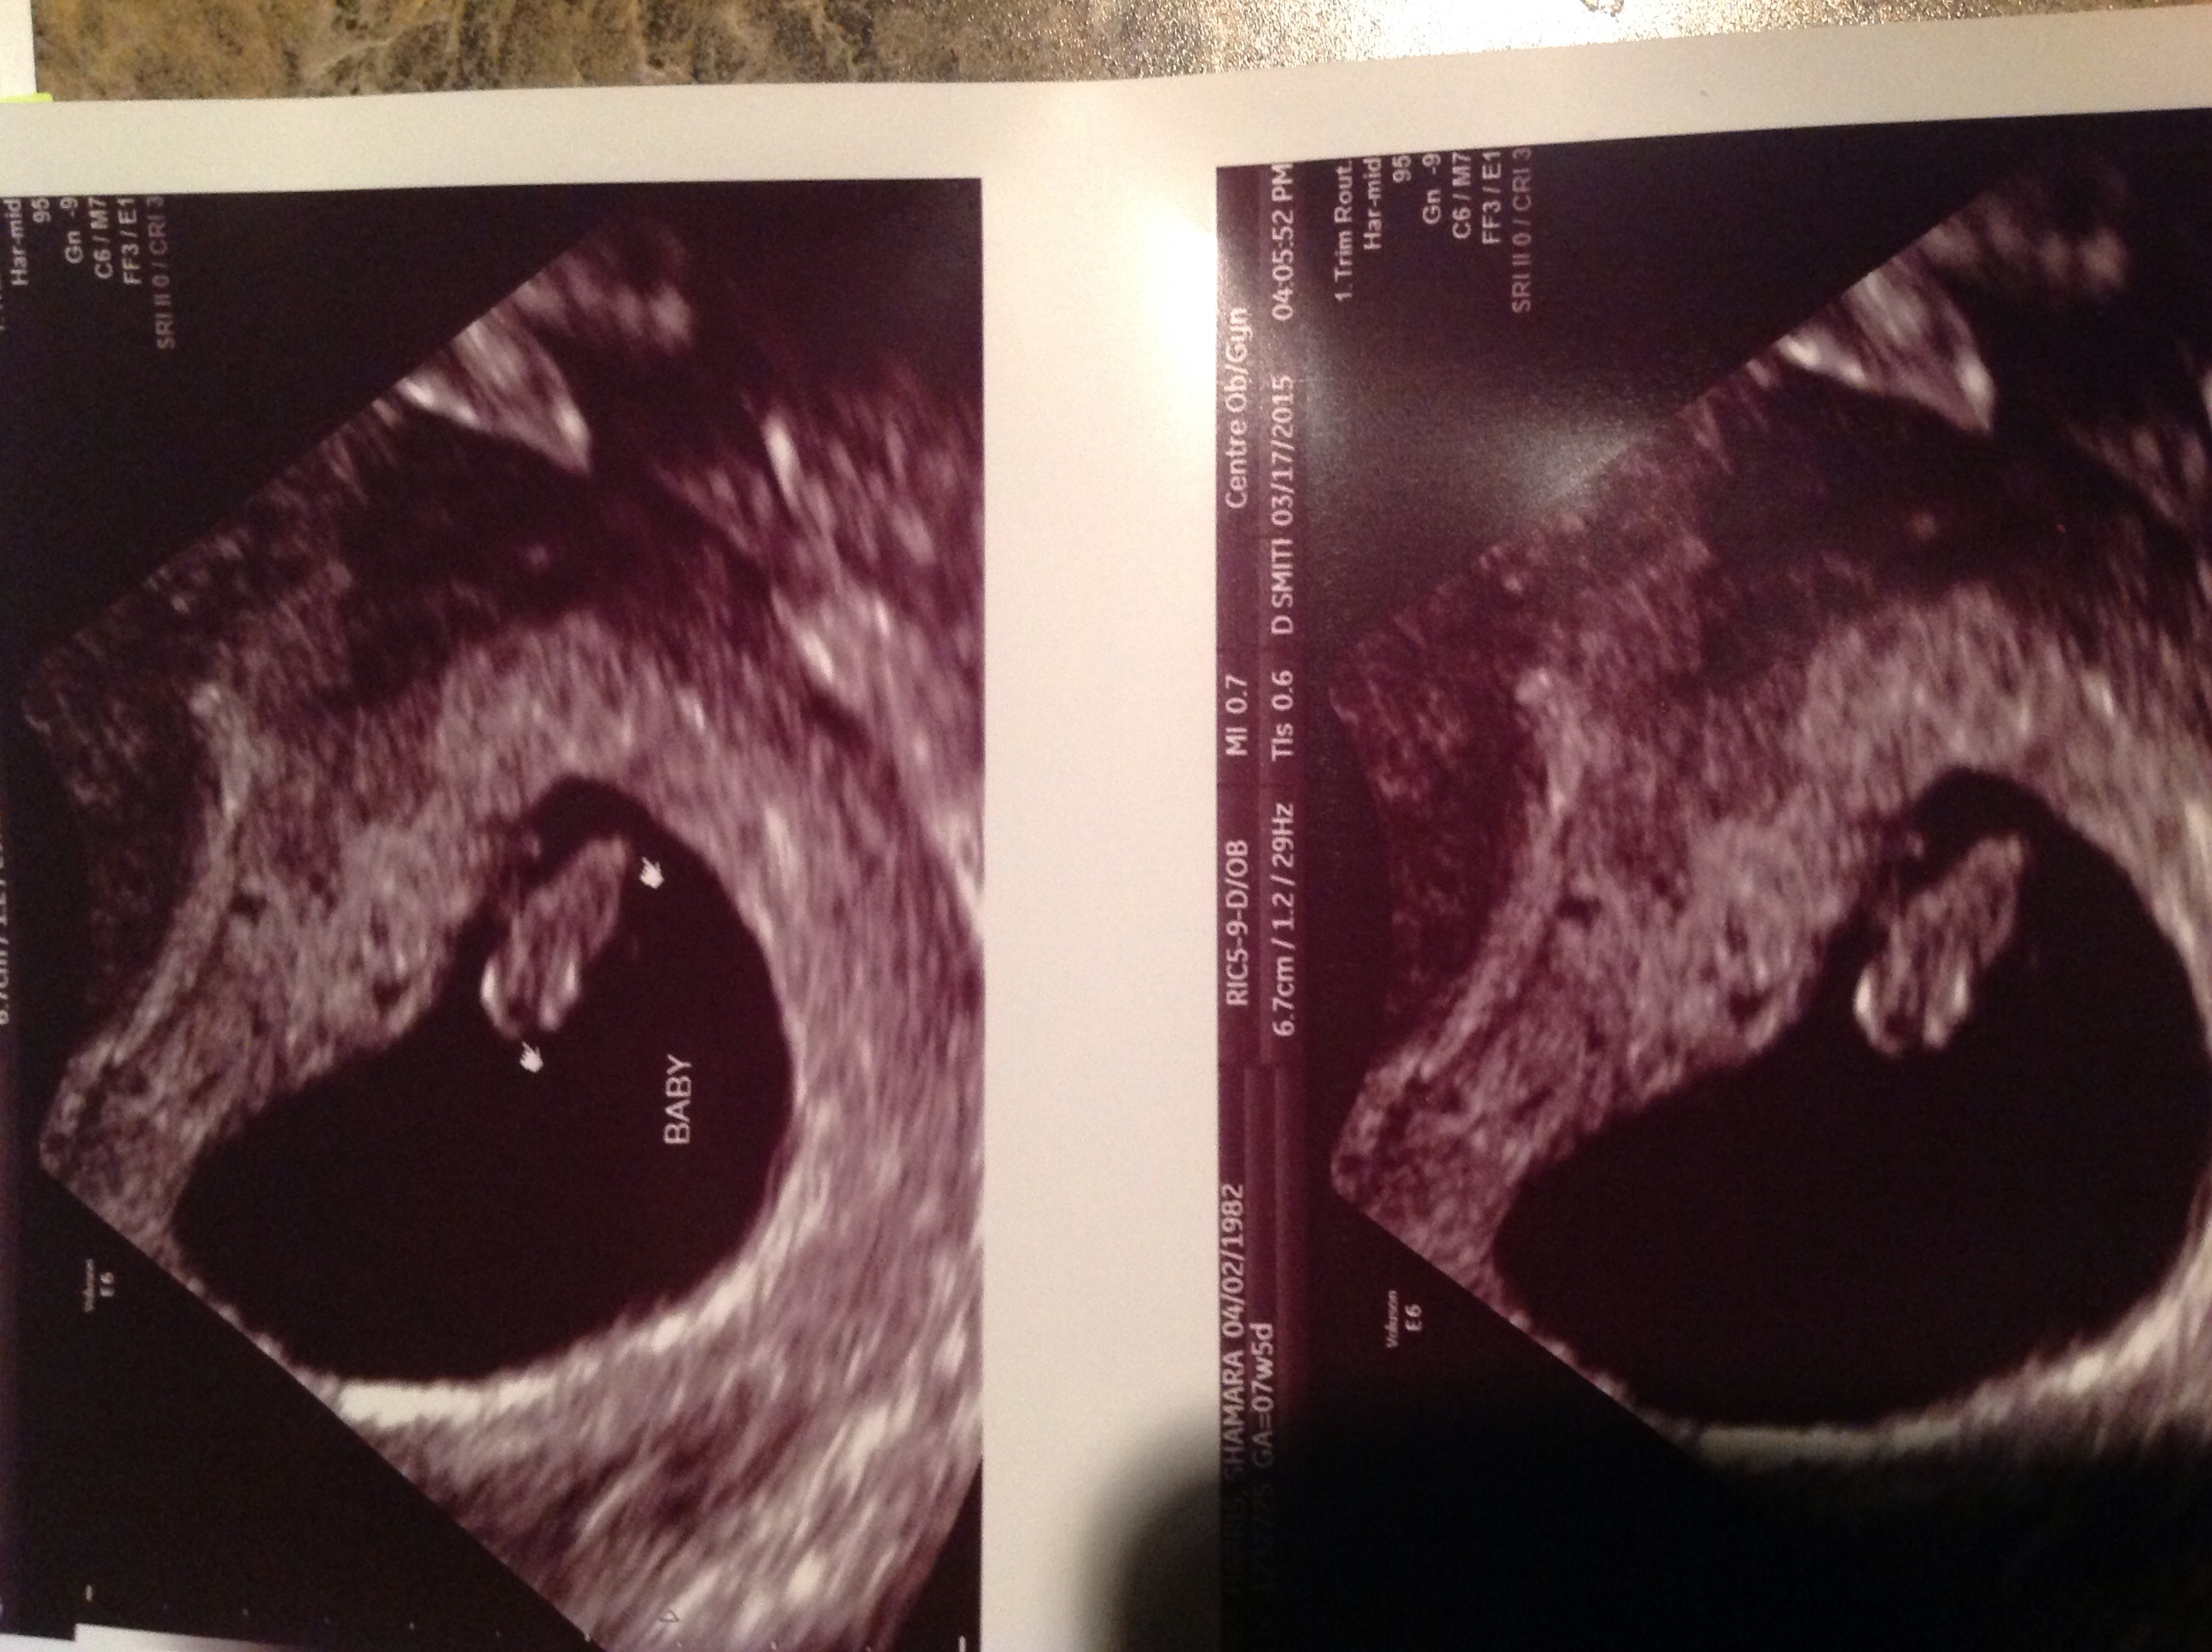

I had an u/s at 5wks to determine my due date (I was unsure of my LMP as it was a mid-pack bleed...yeah my OCPs failed haha!), and another at 7 to confirm. Only a yolk sac was visible w/ the first one. The 7 week u/s seems to also conform that I'm having a hamster! :P